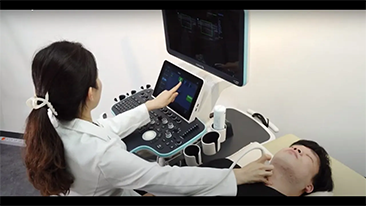

Mindray? ??? ??? ?? ??? ???? ??? ?? ??? ??? ????? ??? ????. ?? ???? ZONE Sonography? ??? ???? ?? Resona 7? ??? ZST+ ???? ?? ?? ? ?? ??? ????? ?? ??? ??? ??? ? ?? ????.

?? Resona 7? ???? ??? ?? ???? ??? ??? ???? ??? ?? ???? V Flow? ?? CNS ??? ?? 3D ??? ???? ?? ???? ?? ??? ?? ?? ?? ??? ??????. ???? ??? ??? ?? ?? ??? ??? ?? ?? ??? ??? Resona 7? ??? ???? ???? ??? ??? ??? ????.